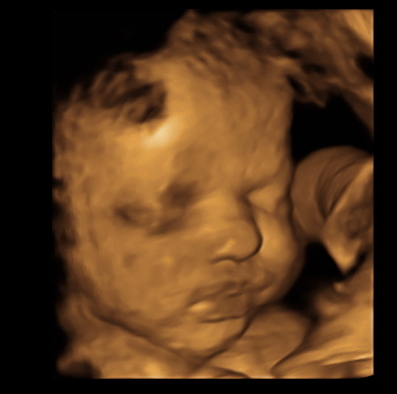

Just got back from my weekly ultrasound and 2 week doctor appointment. Everything still looks great for the both of us. She even flipped back head down from last week. We got some cute shots of her. Here are a few: (I love the one of her sticking her tongue out)

Had a 32 week ultrasound today to check the distance of my placenta to my cervix because it was too close at my 20 week scan. But, thank goodness, as my uterus stretched, my placenta moved up so I'm safe from a scheduled c-section! Woohoo! Also, everything else with baby looked good. He's head down, which means I've been rubbing and talking to his BUTT for the past couple weeks. Best part was the tech got us a couple 3D pics which we didn't expect. He definitely has daddy's flat bridge nose. him.